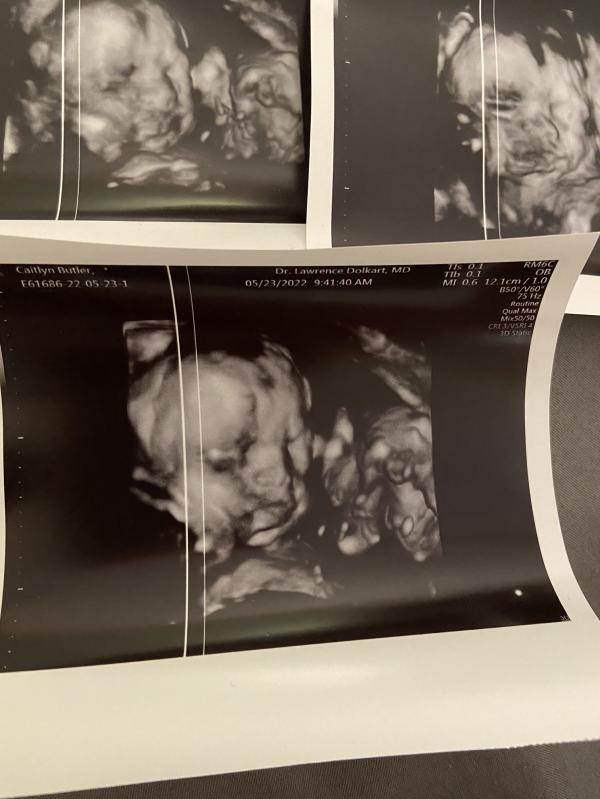

Baby boy is getting so big